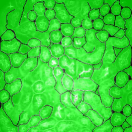

The first row in Figure 3 displays an original microscopy image (), its inhomogeneity corrected version (), and manually delineated groundtruth (), respectively. For brevity we have omitted the superscript in the notation. The second row shows segmentation results of various 3D methods such as 3D region-based active contours [10] (3Dac), 3D active contours with inhomogeneity correction [11] (3DacIC), and 3D Squassh presented in [12] (3Dsquassh). Similarly, the third row portrays various segmentation methods particularly designed for tubular structure segmentation such as ellipse fitting method presented in [15] (Ellipse Fitting), the Jelly filling method in [20] (Jelly Filling), and tubule segmentation using steerable filter [21] (Steerable Filter). Finally, the last row shows segmentation results of our proposed CNN architecture without inhomogeneity correction [27] (2DCNN) and with inhomogeneity correction (2DCNNIC).

For visual comparison we highlighted groundtruth regions in red, segmented tubule regions in green, and background in black. As observed in Figure 3, our proposed method appeared to perform better than the other six methods shown in the second and third rows by distinguishing tubules and was similar performance to 2DCNN. Note that since some methods such as Ellipse Fitting, Jelly Filling, and Steerable Filter only segmented boundaries of tubule structures, tubule interiors were filled in order to perform a fair comparison using connected components with a -neighborhood systems. Also, based on the assumption that tubule regions should contain lumen, if a filled region contained lumen pixel, the region was identified as a tubule region. However, if a filled region did not contain any lumen pixels, the region was considered as a background region.

The segmentation results shown in the second row generally missed many tubule regions. More specifically, 3Dac and 3Dsquassh could not capture the tubular structures but captured some in the center regions due to the intensity inhomogeneity of microscopy images. 3DacIC failed to segment tubular structures but captured multiple lumens inside tubules as well as some tubule boundaries. In contrast, the segmentation results displayed in the third row showed falsely detected tubules. The main reason is that these tubule segmentation methods focused only on detecting boundaries of tubular structures. In particular, due to weak/blurry edges of fluorescence microscopy images, many boundaries were not continuous causing the filling operation to overflow from one tubule to another or to the background regions. The segmentation results using the CNN generally successfully segmented and identified each tubule region.

Figure 4 provides an alternative way to show the segmentation results. In particular, yellow regions correspond to true positives which are pixel locations that are identified as tubules in both the groundtruth and segmentation results. Green regions correspond to false positives which are pixel locations that are identified as background in groundtruth but tubules in segmentation results. Similarly, red pixels correspond to false negatives, namely pixel locations identified as tubules in the groundtruth but background in segmentation results, and black pixel regions correspond to true negative that are identified as background in both groundtruth and segmentation results. The green regions indicate Type-I error (false alarm) regions and the red regions represent Type-II error (miss) regions. As observed from Figure 4, the segmentation results in the first row contained large red regions which mean large regions of tubules were missed. Conversely, the segmentation results shown in the second row contained many green regions indicating many background regions were falsely segmented as tubule regions. In contrast, the segmentation results in the third row had reasonably small green regions and red regions which indicate that the deep learning based segmentation results had higher pixel accuracy with relatively low Type-I and Type-II errors.

For visual evaluation we provide the segmentation results of the proposed method using two different datasets: and , sampled at different depths within the volumes. The first row shows original microscopy images , , and from and the second row displays the segmentation results corresponding to the first row. To better visualize the segmentation results, we highlighted individual tubules with different colors and overlaid them onto the original microscopy images. Similarly, the third row exhibits original microscopy images , , and from . Their corresponding segmentation results are shown in the fourth row. Note that the model which was trained on was used for during the inference stage. Although the shape, size, and orientation of tubular structures presented in are all different from , the proposed method can still successfully segment and identify individual tubules presented in as well as individual tubules in .